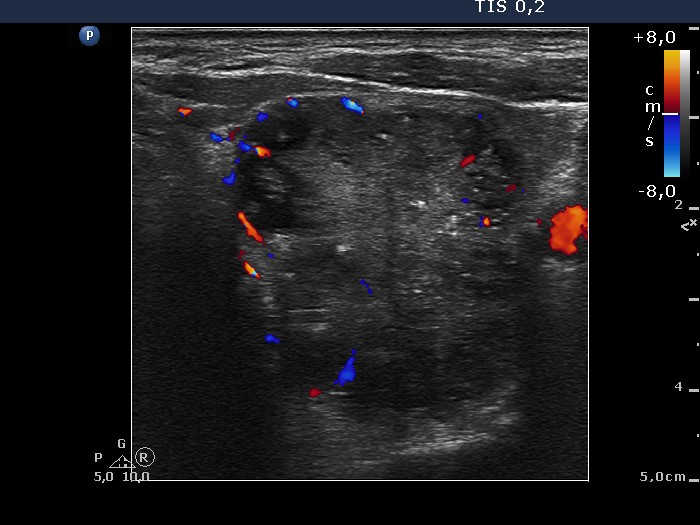

Left lobe, transverse scan, color Doppler mode. The nodule presents signs of intranodular blood flow.